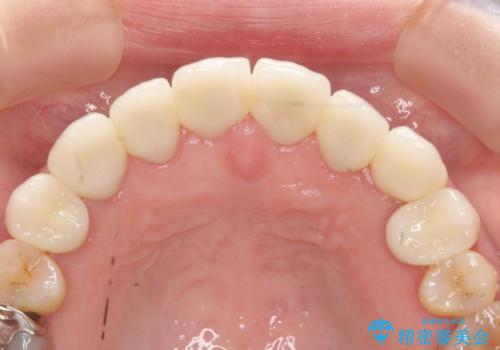

- 上下顎前歯部の見た目が気になるといらっしゃった方の症例です。

上顎は左4番から右4番までの8歯、下顎は左3番から右3番までの6歯、計14歯をオールセラミッククラウンにより補綴しました。